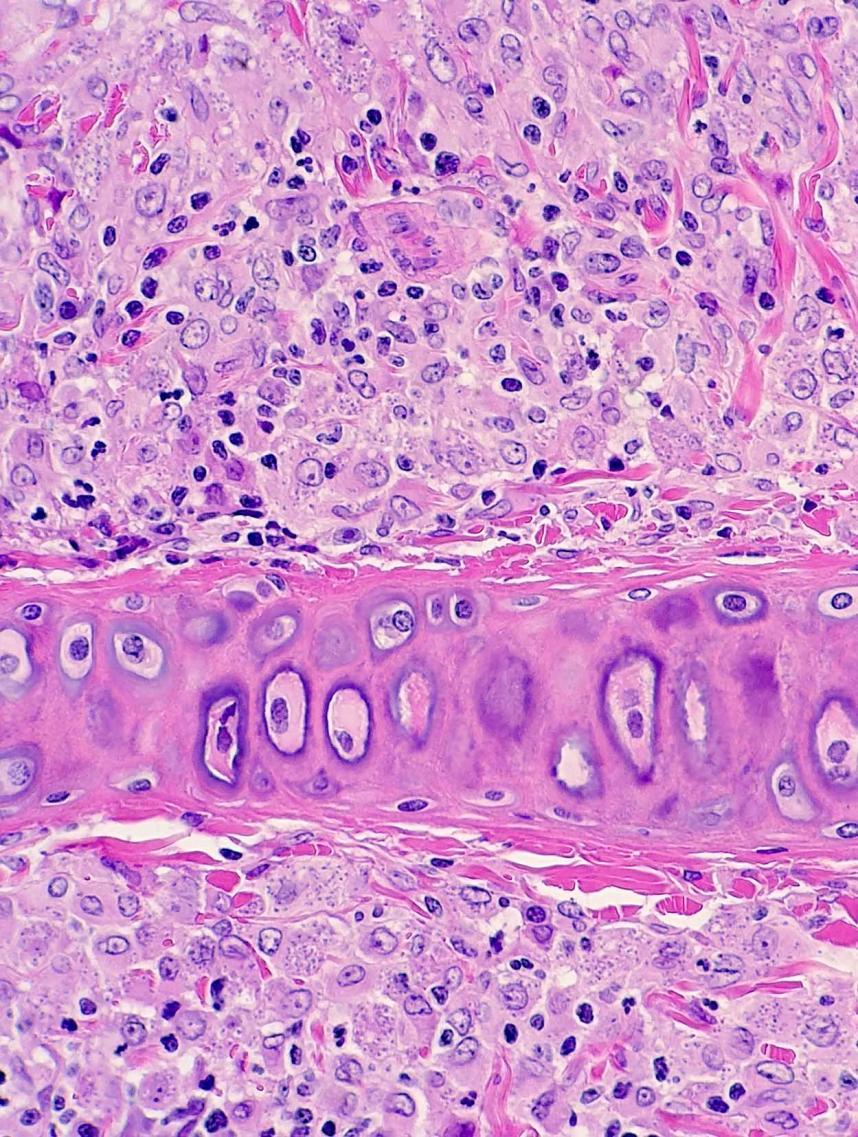

Leishmaniasis en hurón

Ésta es la primera descripción de leishmaniasis en un hurón, eficaz y diligentemente trabajada, como siempre, por Jacobo Giner de Centro Veterinario Menescalia, con la colaboración de la Universidad de Zaragoza y publicada en Veterinary Parasitology: Regional Studies and Reports 19:100369, 2020. doi: 10.1016/j.vprsr.2020.100369. Con esta publicación, Jacobo logró el 2º premio de los Premios de Divulgación Científica 2020 del Ilustre Colegio de Veterinarios de Valencia; aunque Jacobo está acostumbrado a ganar premios y seguro que tiene entre ceja y ceja el primer premio, nuestras más sinceras felicitaciones por este extraordinario logro y ánimos para que siga persiguiendo el primer premio y así pueda invitarme a esas cenas que me debe en el restaurante de cocina de autor Almoraduz, Puerto Escondido (Oaxaca). No se pierdan el taller de Medicina y Patología de Hurones del Congreso Solidario de Medicina y Conservación de Fauna Exótica y Salvaje de Puerto Escondido con Jacobo, Mike Garner y un servidor, va a ser extraordinariamente rico en medicina, patología y humor...cuando de una vez por todas podamos celebrar este congreso. ¡Bravo, Jacobo!.